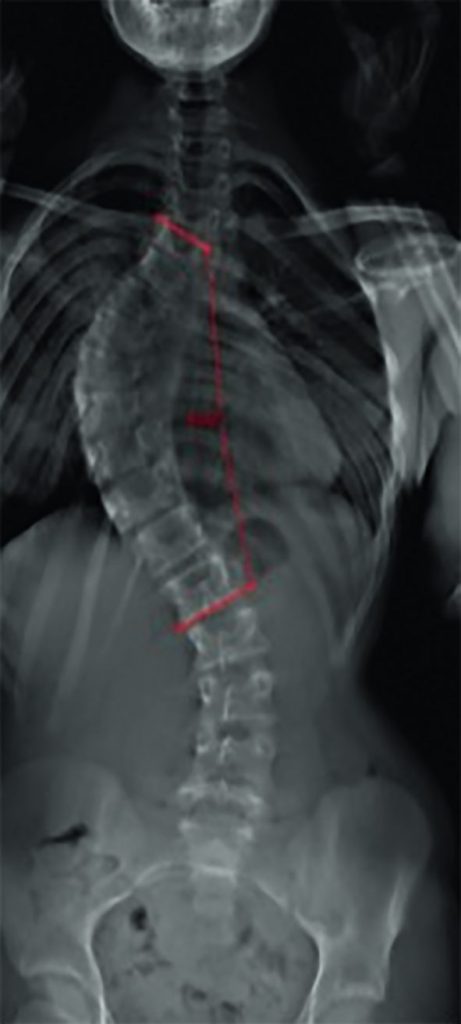

Fig. 119.4 Jeune fille de 12 ans. Cliché Eos® de face.

Scoliose thoracique idiopathique à convexité droite dont les vertèbres sommet sont les vertèbres T4 et L1. L’angle de Cobb, ici mesuré en 2D, quantifie la scoliose.

Source : CERF, CNEBMN, 2022.